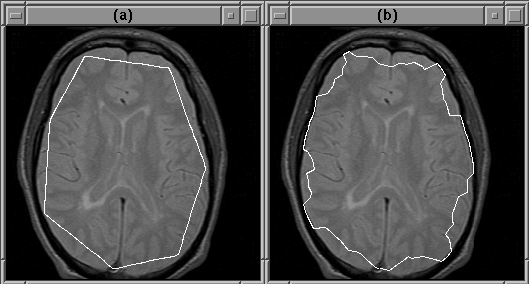

Figure 5.10 shows a case where the igraph of Figure 5.8 fails even though the initial contour provided by the user is reasonable. In this case the deformable contour attached itself to the wrong edge.

Figure 5.10: The active contour model can fail to detect the intracranial boundary. The contour attaches itself to the edge of another feature instead. (a) The initial guess. (b) The converged contour.

As mentioned previously, this problem can be remedied by incorporating the gradient direction into the active contour model algorithm. Figure 5.11 shows the igraph of Figure 5.8 modified to use gradient direction. The active contour model operator, mriSnakes2D2, utilizes both gradient direction and balloon forces.

Given the same initial guess as that in Figure 5.10, and with balloon forces disabled, mriSnakes2D2 produced better results than mriSnakes2D. Figure 5.12 shows that the correct edges are found.

Figure 5.12: The deformable contour attaches itself to the edge of the intracranial boundary because the edges of the other features run in the wrong directions. (a) The initial guess. (b) The converged contour.